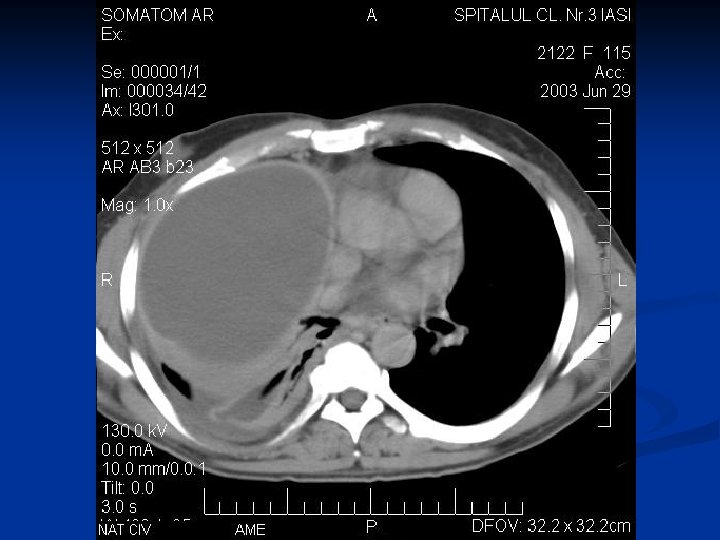

Caracteristici generale n n n Boala parazitara determinata de Taenia echinococcus granulosus. Descrisa inca de pe vremea lui Hipocrat si a lui Galen. Termenul de “chist hidatic” utilizat de Rudolphi in 1908. Localizarea pulmonara este a doua ca frecventa dupa cea hepatica. Boala cu distributie endemica in regiunea mediteraneana, Orientul Mijlociu, Australia, Noua Zeelanda, America de Sud.

Material si Metoda n Studiul de fata analizeaza retrospectiv 162 de cazuri operate in perioada 1999 – 2003.

Metode de diagnosticare

Concluzii n n n CHP evolueaza mult timp asimptomatic sau cu simptome nespecifice. Diagnosticul

Concluzii n n n CHP evolueaza mult timp asimptomatic sau cu simptome nespecifice. Diagnosticul precoce este deosebit de important avand in vedere evolutia acestei boli. Tratamentul medical antiparazitar (Albendazol) este indicat postoperator. Rezectia pulmonara este o metoda de rezerva in tratamentul chirurgical al CHP. Indicatia operatorie este absoluta, tehnica operatorie alegandu-se in functie de caracteristicile fiecarui caz in parte.